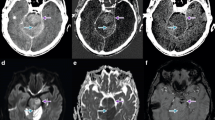

Example of ischaemic lesions in the caudate nucleus (violet arrow) and putamen (blue arrow) in the BW (A), VNC (B) and EM (C) series. In the BW (A) and VNC (B) series, the lesions are not clearly visible, however in the EM the hypodense infarctions can be clearly identified. Follow-up CT with infarction delineation (D)

The lowest infarction densities were found in the EM series (1.6 ± 14.1 HU), followed by the VNC series (25.4 ± 3.1 HU), and the BW series (37.5 ± 3.5 HU). The highest CIDs were displayed with the EM series (73.3 ± 49.3 HU), higher than with the VNC series (8.3 ± 4.7 HU) and the BW series (-1.72 ± 13.3 HU). In the EM series, the peripheral infarction density (8.67 ± 26.13 HU) was higher than the infratentorial infarction density (-2.72 ± 50.07 HU) and density of the central infarctions (-4.44 ± 57.59 HU; p = 0.628). The inter-rater agreement of the density measurements and infarction volumetrics was excellent (Table 1).

Rater 1 identified 99 (90.0%) and rater 2 identified 100 (90.9%) of the overall 110 infarctions present in the EM series in the early stage after endovascular therapy, significantly more than using the VNC or BW series (chi-square test, p < 0.01). The detectability of the infarctions was statistically independent from the localisation of the infarction: rater 1 identified 44 of 46 deep cerebral infarctions and 44 of 49 superficial infarctions in the EM series; rater 2 identified 45 of 46 deep cerebral infarctions and 44 of 49 superficial infarctions in the EM series. Furthermore, rater 1 identified 88 of the 95 supratentorial and 11 of 15 infratentorial infarctions in the EM series; rater 2 identified 89 of 95 of supratentorial and 11 of 15 infratentorial infarctions in the EM series.

In the subjective visual evaluations, the EM series revealed the significantly highest visible infarction contrast (2.30 ± 1.20; p < 0.01 each) but also the most severe subjective image noise (2.37 ± 0.70; p < 0.01 each). Infarction contrast was considerably lower in the VNC series (3.25 ± 0.85) and lowest in the BW series (3.57 ± 0.70; p = 0.02). The least pronounced image noise was found in the BW series (1.21 ± 0.51), with only slightly lower values in the VNC (1.28 ± 0.55; p = 1.00; Table 3). Haemorrhagic transformations developed in four of the infarctions (3.6%; 9% of patients) – in one case in the right insula, one in the right putamen, one in the left thalamus and one in the left caudate nucleus.

In this study, modified VNC series were reconstructed from the data sets of DECT examinations immediately after EST, which enabled better visualisation of early cerebral infarctions than a standard BW or VNC series. The series was called the ‘oedema map’ (EM) and it can be described as a modified GM-water map [9] that is generated by TMDT and was first used to detect infarctions after EST. The three ‘materials’ are GM, WM and water, with partial subtraction of the lipid content. The EM series displayed significantly lower objective density values of the infarctions and higher density differences between infarctions and the respective contralateral areas, presumed to represent the detectability of an infarction, than the other evaluated series. The subjective detectability of the infarctions with the EM series demonstrated almost perfect sensitivity, specificity and a large AUC, and was thus superior to the other series despite having the highest image noise. The reproducibility between the raters was high.